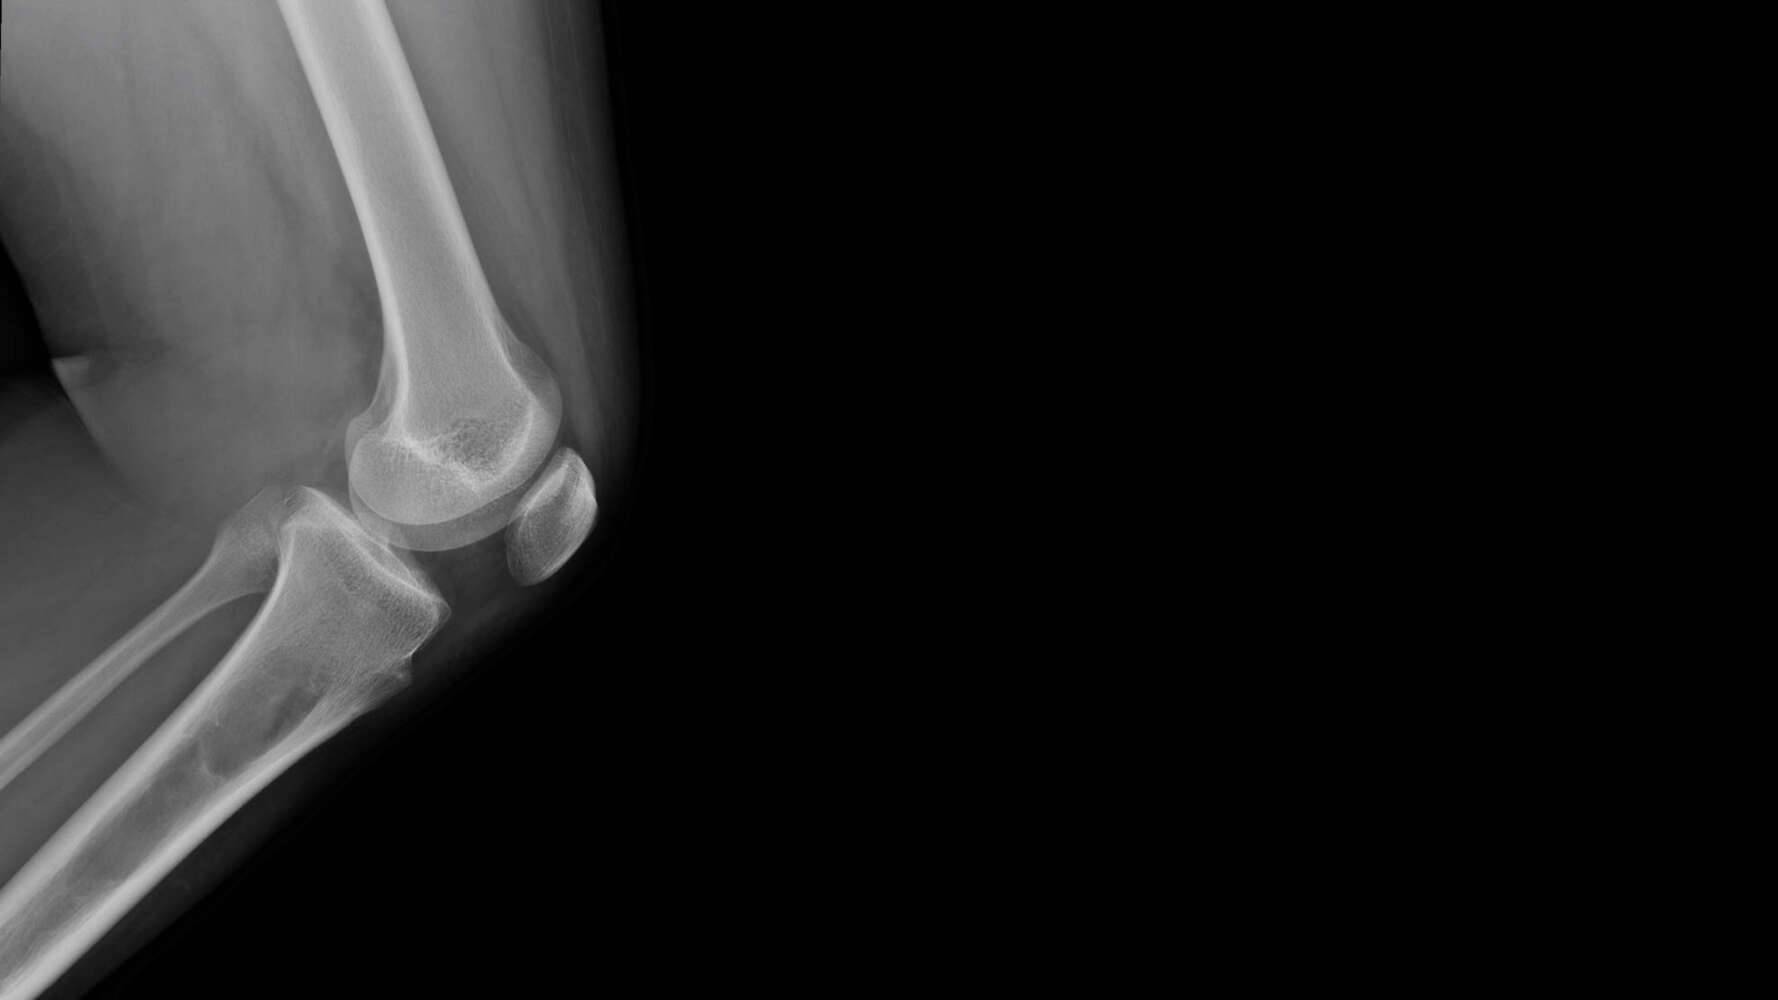

Osteosarkom. Diese Krebsart macht etwa 20% (2) aller primären Knochentumore aus und tritt meist bei Kindern und Jugendlichen auf. Er tritt in der Regel in den langen Knochen um das Knie herum auf, kann aber in jedem Knochen vorkommen. Die Symptome können eine ganze Zeit lang auftreten, bevor die Patienten einen Arzt aufsuchen.

Um Knochenkrebs sichtbar zu machen, müssen sich Patienten bildgebenden Untersuchungen wie Röntgenaufnahmen, CT-Scans oder MRT-Scans unterziehen. Diese Untersuchungen liefern hochwertige Bilder von den Strukturen im Körper, einschließlich der Knochen. Manchmal zeigt sich Knochenkrebs als große, unregelmäßig geformte Masse, aber das kann von Patienten zu Patienten unterschiedlich sein. Um die Bilder zu interpretieren, wird ein Radiologe benötigt.